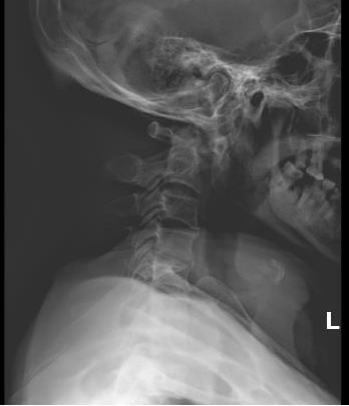

术前与术后对比图

经过充分的术前准备,由肖丹博士、黄勇兄副主任和我院张勇华主任及骨科一区团队共同为黄先生进行了手术治疗。术后黄先生顺利恢复,四肢麻木、乏力显著好转,排尿、排便恢复正常。出院时黄先生称赞道:多亏了省人医的帮扶专家,可以让自己在家门口享受到省级医院的待遇!